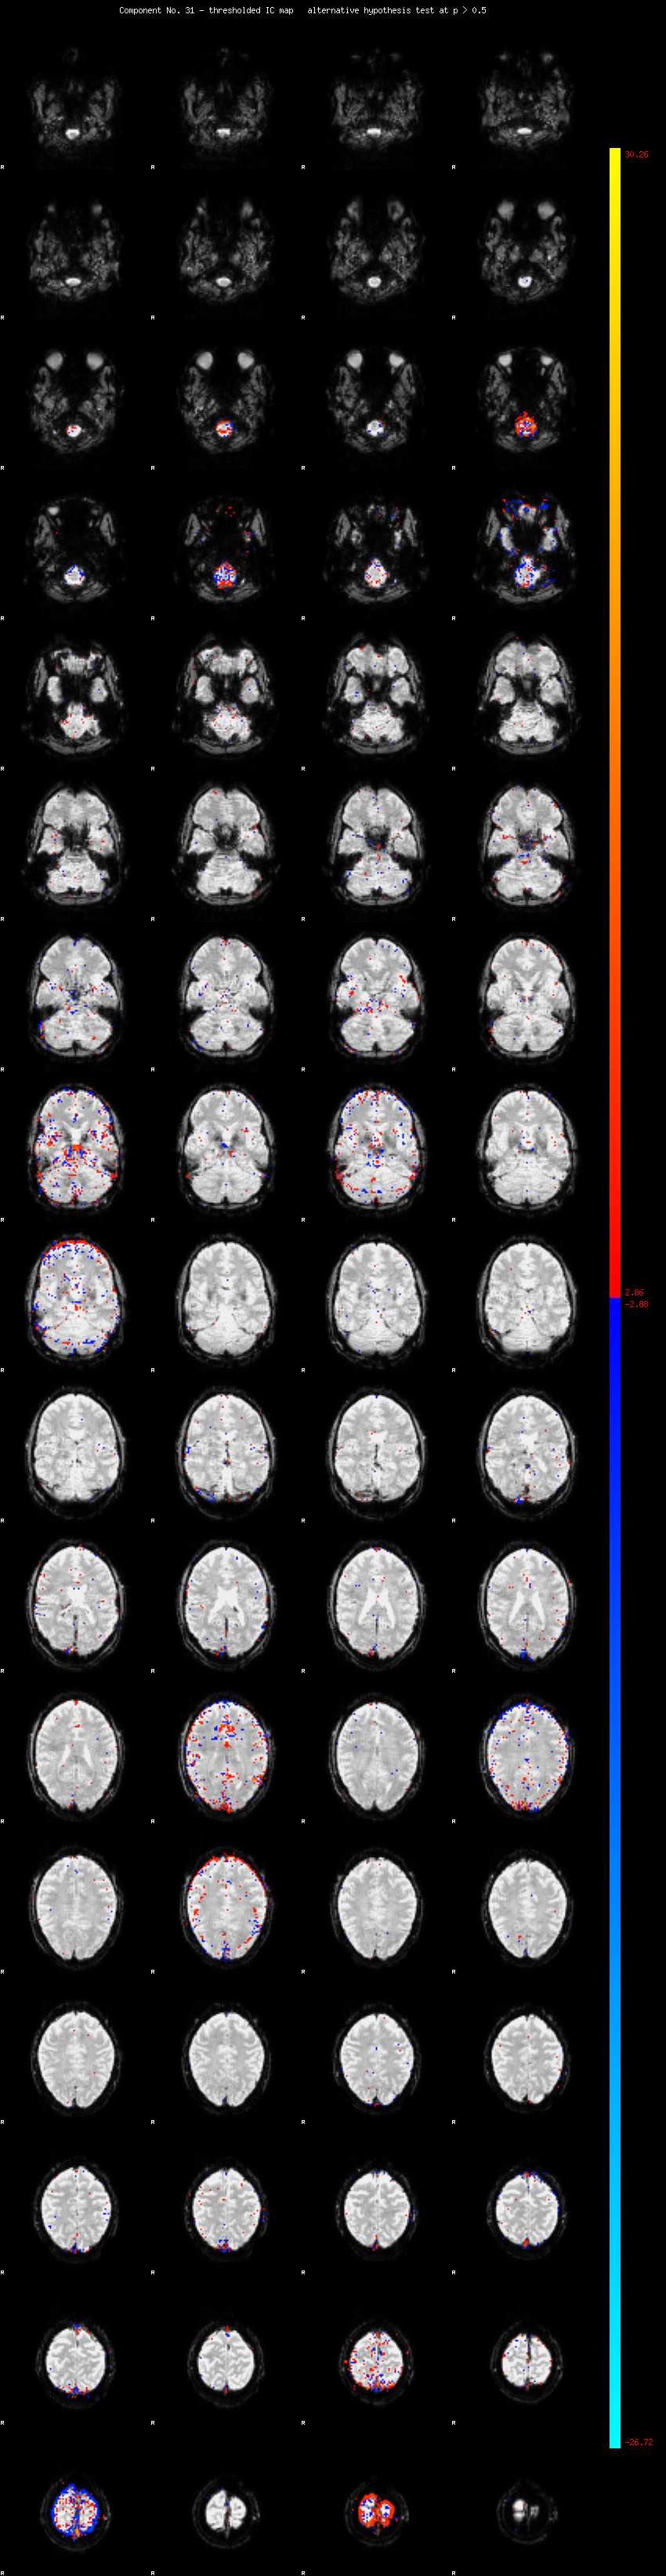

MELODIC Component 31

1.21 % of explained variance;     0.81 % of total variance

MMfit